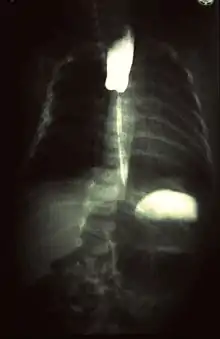

Les produits barytés (contenant du sulfate de baryum), non-hydrosolubles, atténuent également les rayons X et permettent d'obtenir un meilleur contraste sur le cliché radiologique. On s'en sert pour remplir le tractus digestif et réaliser différents examens radiologiques permettant d'imager le larynx, l'œsophage, l'estomac, l'intestin grêle et le côlon. Ces produits sont absorbés par voie haute ou basse. Ces produits sont formellement contre-indiqués en cas de brèches ou de perforations de la paroi digestive.